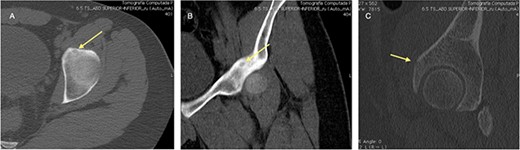

An 18-year-old male with 18 months of left hip pain was referred to an orthopedic surgeon for evaluation. Pain occurred with all hip movements, predominantly at night. Physical examination of the hip showed pain with deep palpation on the groin and positive test for flexion adduction and internal rotation and Patrick test. X-rays were obtained and femoroacetabular impingement (FAI) with labral tear was suspected (Fig. 1). A magnetic resonance imaging (MRI) showed no hip labrum or chondral defect. Measurements for bone deformities of cam and pincer were normal. Physical therapy and nonsteroidal anti-inflammatory drugs were prescribed with some pain relief especially at night. After no improvement of symptoms he was evaluated by a hip surgeon. Intra-articular hip injection with steroids was given and pain disappeared but nocturnal pain recurred after 24 h. Due to the clinical setting and poor response to pain management, an OO was suspected and (CT) was ordered where a 6 mm sclerotic bone tumor with a nidus in the anterior rim of the left acetabulum was identified and corresponded with the pain localization (Fig. 2).

CT scan of the left hip showing a 6-mm extra-articular OO on the anterior rim of the acetabulum (yellow arrow).